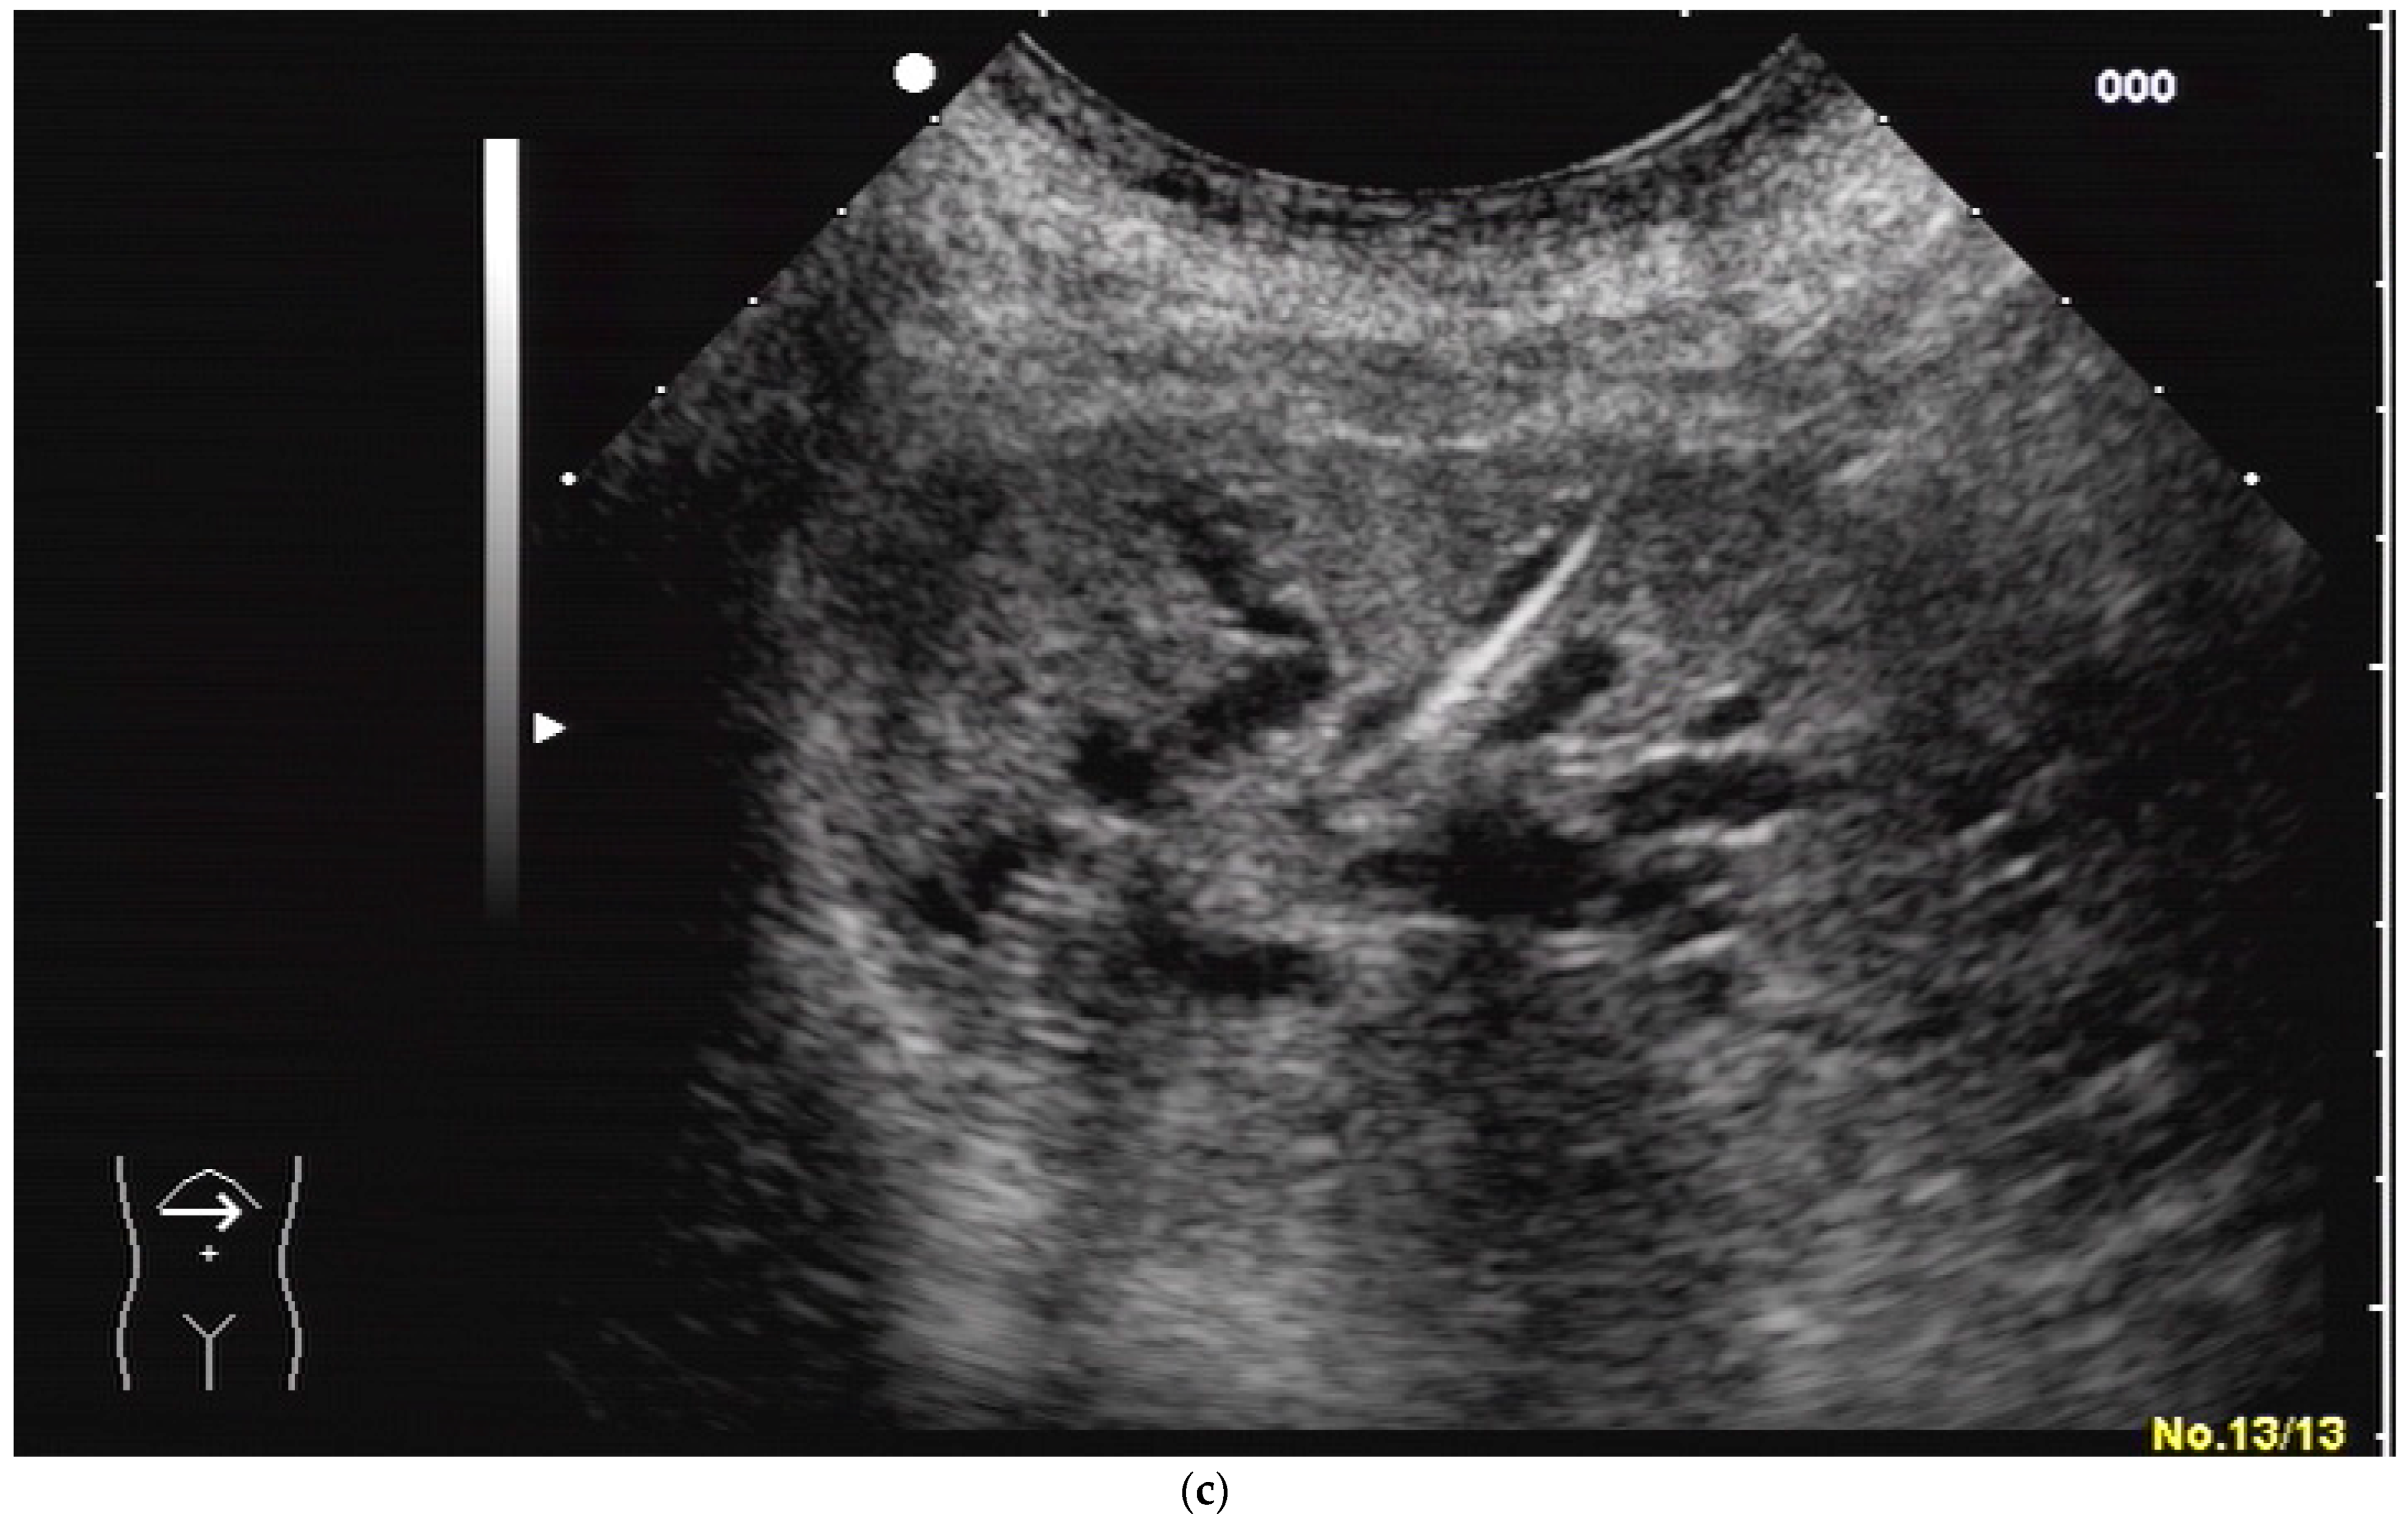

Most authors recommend a transhepatic approach in order to prevent biliary leakage to the abdominal cavity during drainage or after removal of drainage [43,55,56,76,77] (Figure 9).

(a) Transhepatic puncture of an inflamed gall bladder in the in-plane technique. The Chiba needle is depicted well; (b) A few days later, laparoscopic cholecystectomy was performed. The drainage ran through Segment V of the liver. It was removed without provoking biliary leakage from the liver parenchyma.

The consideration is that a perforation in the hepatic surface of the gallbladder will be covered by the liver tissue after the removal of the drain. However, retrospective analyses comparing the transhepatic route with the transperitoneal (i.e., nontranshepatic) access (Figure 10) report no differences in the complication rates [58,78,79].

Figure 10.

PGBD without passing the liver and using the trocar technique: straightened drainage passes right below the lower liver margin into the gallbladder.

Again, the “in plane” approach is recommended to depict the needle in real time and continuously on its way. This is mandatory because iatrogenic perforation of the posterior gallbladder wall must be avoided. Both the drainage techniques, Seldinger (Figure 11a–c) and trocar (direct puncture, cf. Figure 10), may be used, depending on the physician’s preferences [43,58].